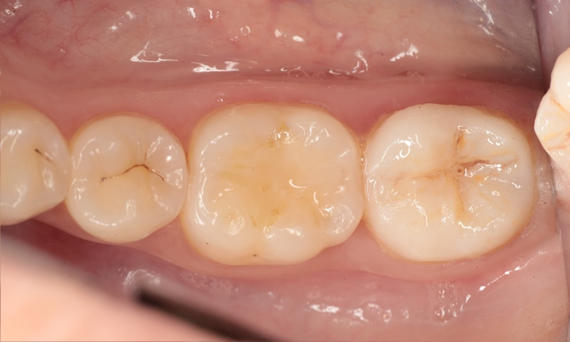

Before: Failed amalgam restoration needing replacement. Patient complaining of sensitivity and tooth presenting multiple cracks.

After: Chairside CAD/CAM partial crown restoration fabricated with CEREC Tessera Advanced Lithium-Disilicate glass ceramic.

Lower second molar chairside restoration

A partial CEREC Tessera crown

A lower second molar with sensitivity presented with cracks as well as an extensive Class I composite restoration on the buccal surface. According to the minimally invasive concept a CAD/CAM partial crown was planned, fabricated and bonded using CEREC Tessera in a single visit.